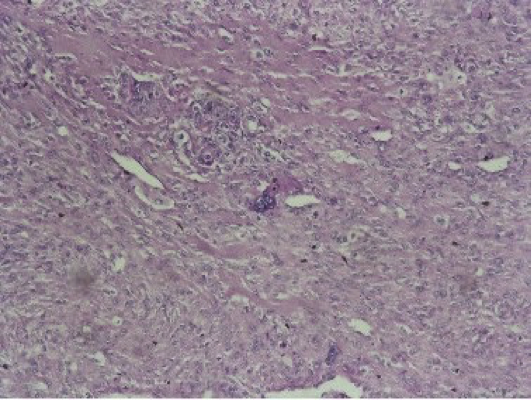

Carcinome mammaire, canalaire infiltrant, symptômes. Le carcinome mammaire est une tumeur qui se forme dans les tissus du sein. Le plus fréquente est le carcinome canalaire. Carcinome canalaire in situ wikipédia. Cancérogénèse de la dysplasie au cancer du sein. Le ccis (carcinome canalaire in situ) se développe à partir des cellules épithéliales tapissant les canaux. Qu'estce qu'un carcinome canalaire infiltrant ? Medisite. Le carcinome canalaire infiltrant est le most cancers du sein le plus fréquent. Parfois appelé adénocarcinome canalaire ou carcinome canalaire envahissant, il. Pathologie mammaire de l’homme pe.Sfrnet. Pathologie mammaire de l’homme b dutouquet, m cagneaux, m dhoossche, n laurent, m lernout, l boulanger, e poncelet provider d’imagerie de la femme. Carcinome canalaire infiltrant santémédecine. Carcinome canalaire infiltrant. Posez votre question nada43 dernière réponse le 19 sept. 2014 à 2101 par hananek. Bonjour, j'ai un most cancers du sein avec des.

Le carcinome canalaire, de l’in situ (cis) vers l’infiltrant. Le carcinome canalaire, de l’in situ (cis) vers l’infiltrant (cci) corrélation radiohistologique à propos de 117 cas e. Daoud(1), m. Elleuche, s. Haddar, h. Anatomie du sein depistagesein.Ca. Anatomie du sein. Le sein est composé d’une glande mammaire, de fibres de soutien (ligaments de cooper) et de graisse (tissu adipeux); le tout est recouvert par l. A.. Anabible dr michels carcinome canalaire infiltrant. Le carcinome canalaire infiltrant représente los angeles grande majorité des carcinomes de l. A. Glande mammaire. Discussion board cancer du sein doctissimo. Pas facile de parler du most cancers, une maladie qui fait peur. Forum d'entraide et de soutien, groupe de dialogue autour de los angeles prevention, des traitements, de la. Dépistage et ponctions guidées du sein emconsulte. Previous article le système birads™ en imagerie mammaire initiation à son utilisation en version française j chabriais, okay kinkel, f thibault.